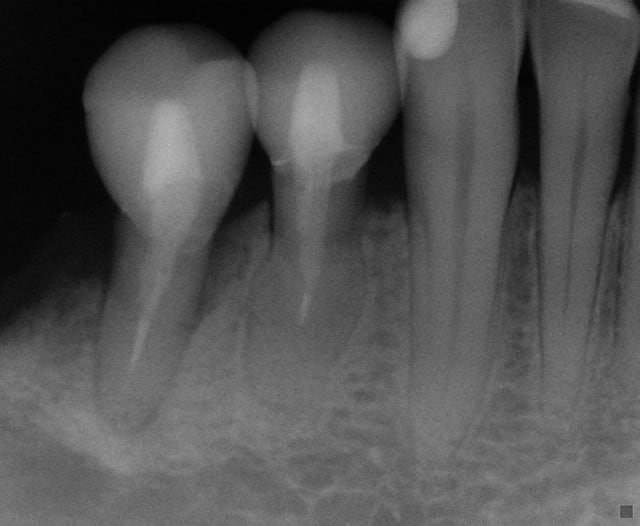

J'ai en effet taillé en pyramide car il ne me restait de valide qu'une partie du pan vestibulaire, et encore bien entamé par une profonde carie du collet heureusement sans contact pulpaire. J'aurai pu rajouter d'avantage de composite en OL, en général j'essaye de coller directement sur la dentine mais là il ne m'en restait que très peu...

J'aurai certainement obtenu un meilleur résultat en réduisant cette pyramide en hauteur forcément en l'aplatissant, mais je ne suis pas certain qu'un pilier plus large aurait changé grand chose, la MCXL gèrant bien les pans inclinés.

Pour ton cas de 2 prémolaires, tu t'en tires bien, mais les dents sont pas très top coté paro, et j'aurais peut-être penser implanto, mais bon....